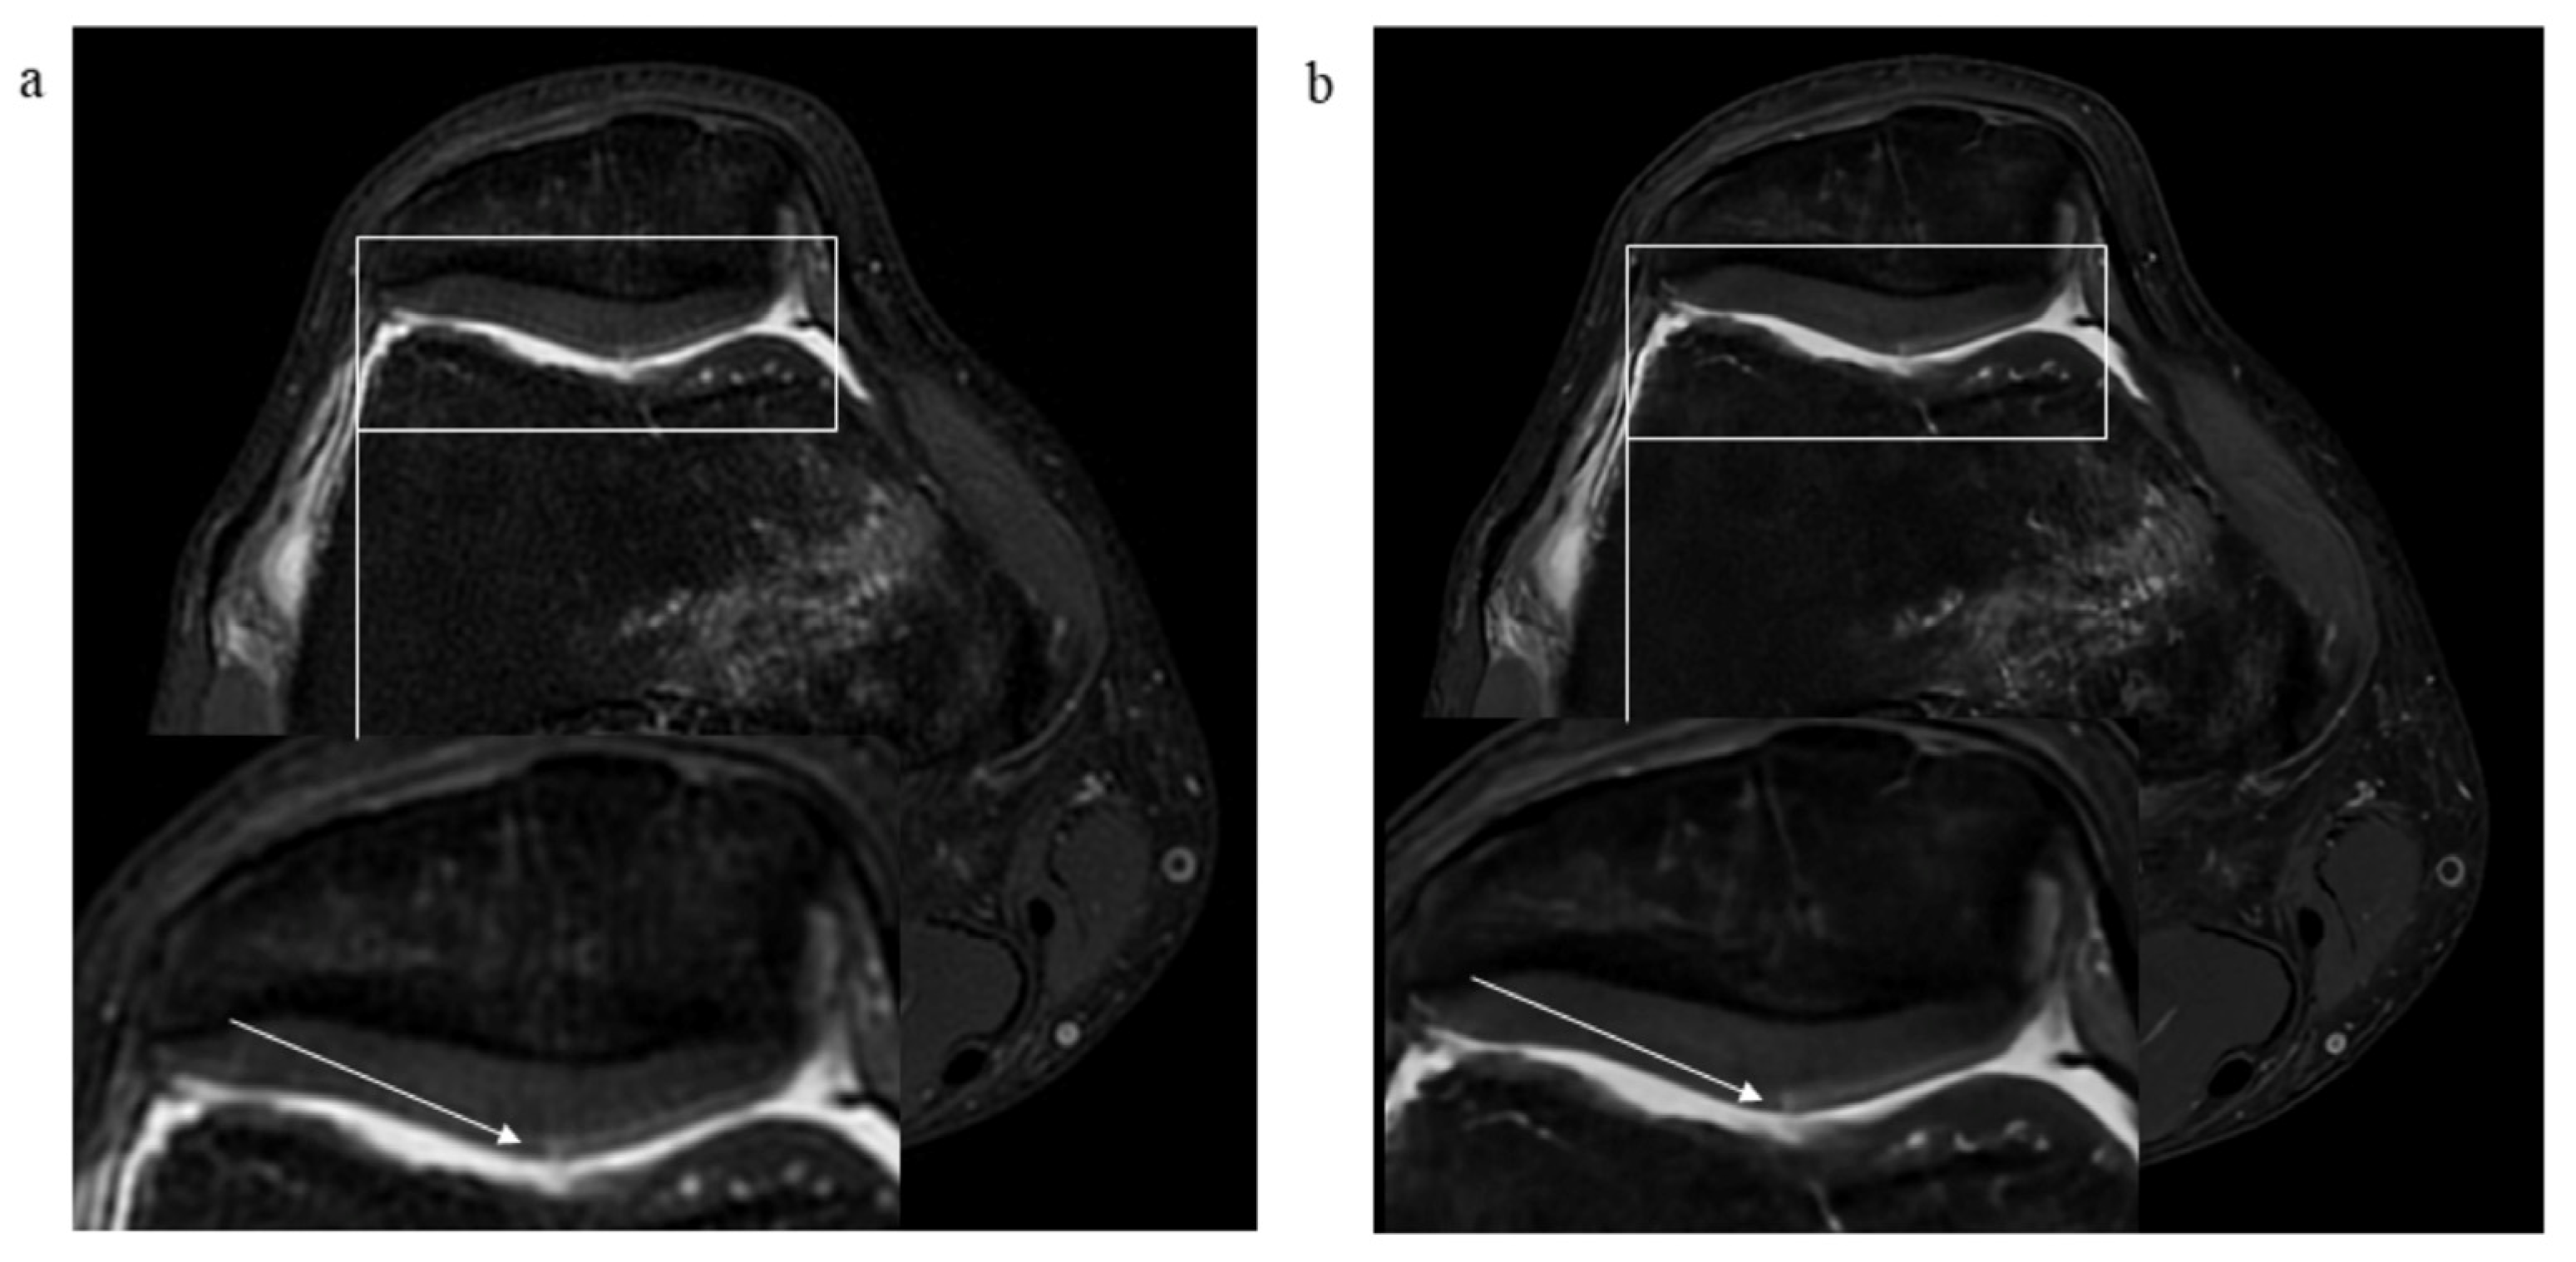

3.2. Pathological Findings